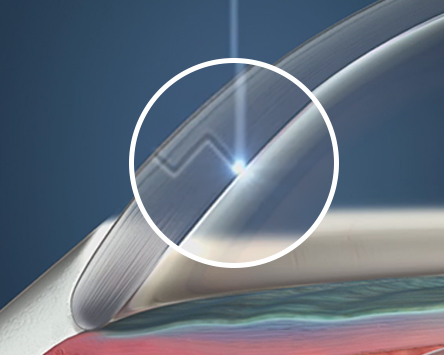

프리미엄 레이저 120º 다면 절개를 이용한

절개부위의 고정으로 충격에 강합니다.

올레이저 노안백내장

절개 부위가 고정된

레이저 다면 절개